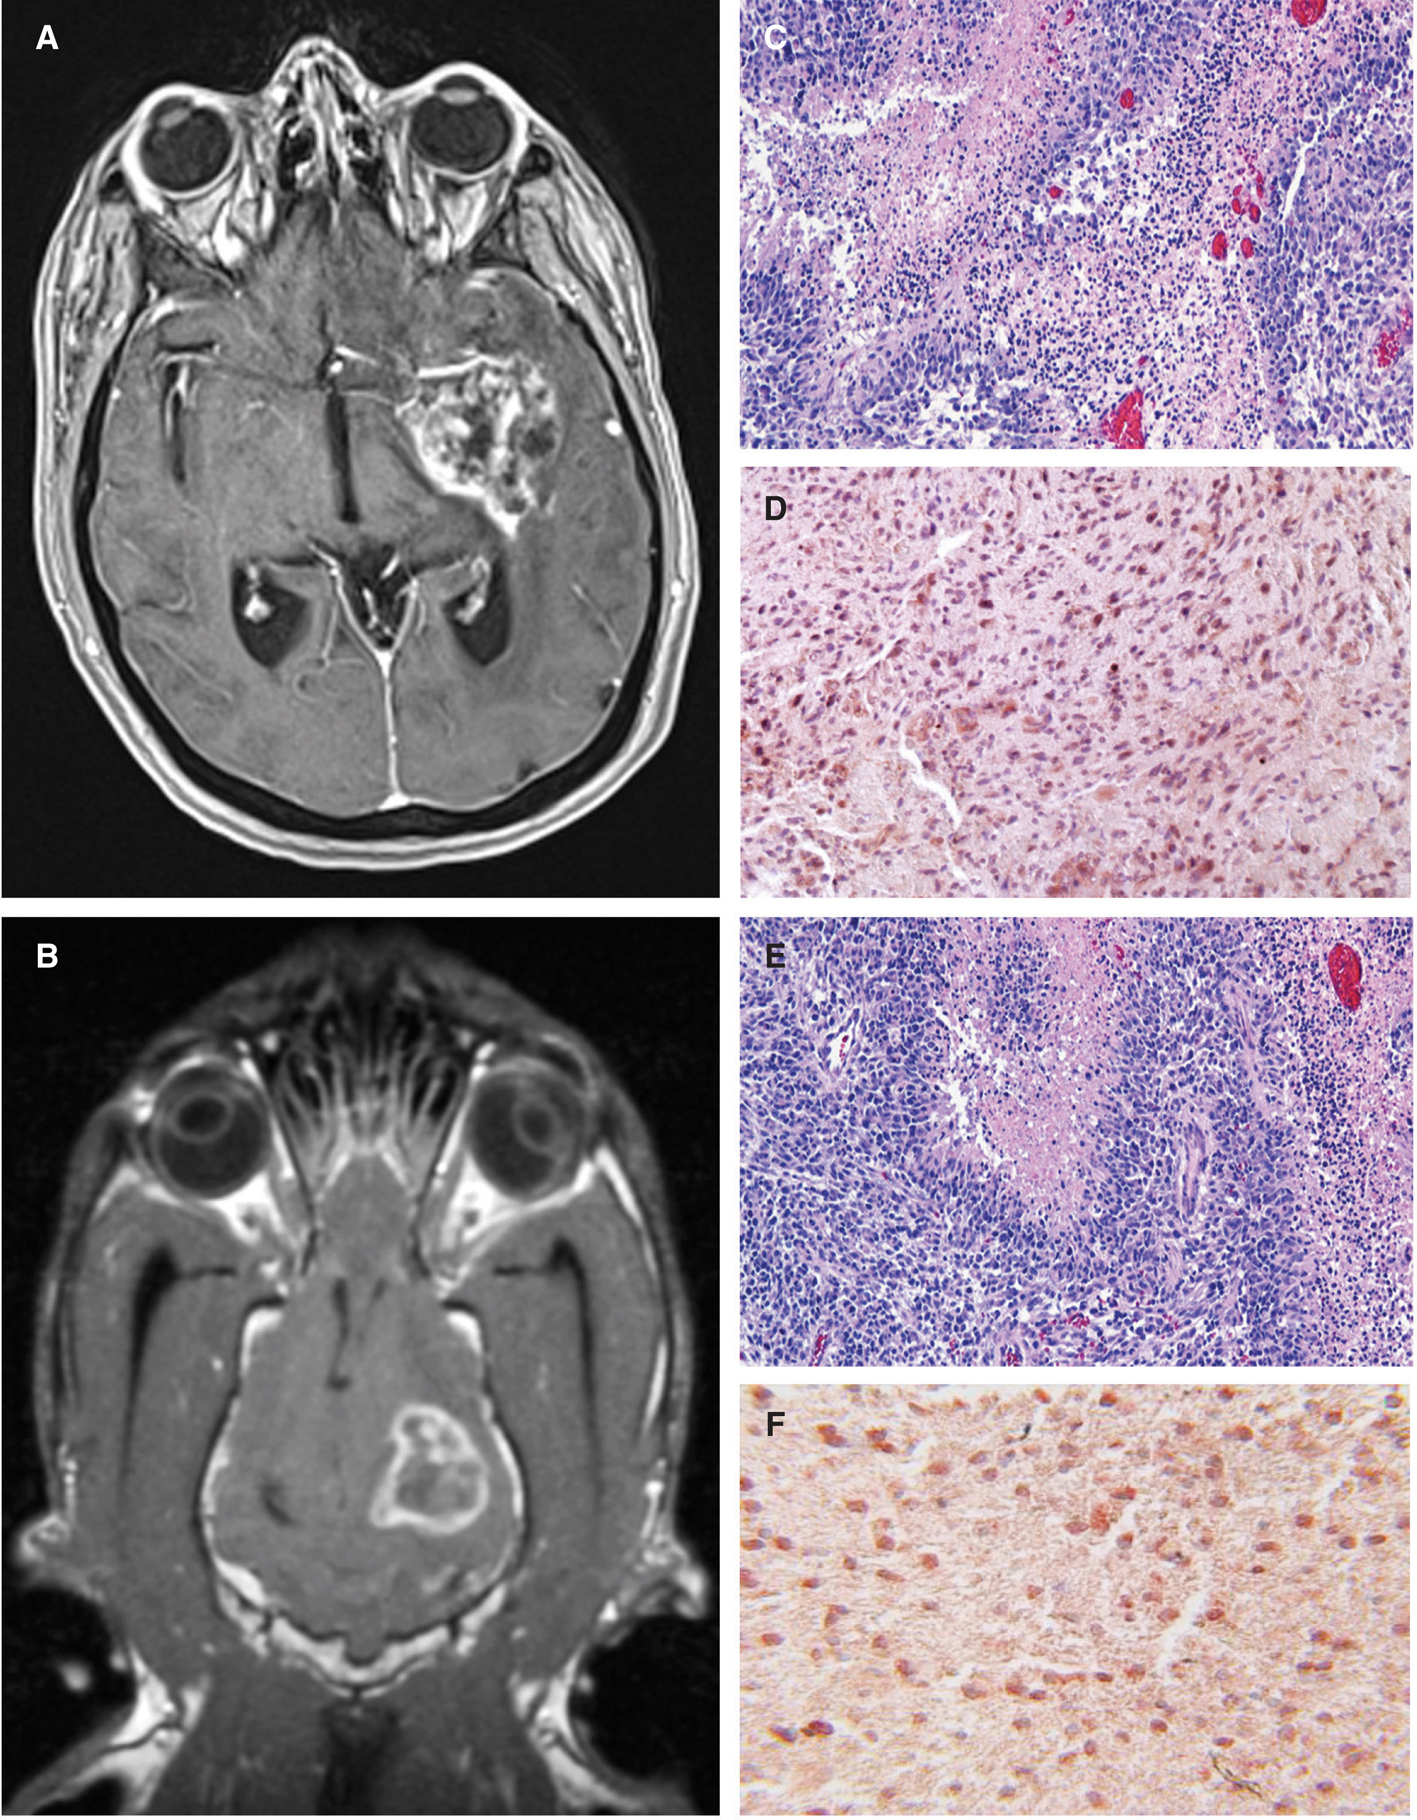

The histopathological and diagnostic imaging features of canine gliomas (Figure 1) are also remarkable similar to their human counterparts (31–35). These shared morphologic features facilitate comparative classification and grading of tumors using World Health Organization criteria (36) and performing objective imaging–based therapeutic response assessments using the Response Assessment in Neuro-Oncology (RANO) system criteria (28, 37). However, the frequency of glioma subtypes encountered in dogs differs from that seen in humans (Table 1), with oligodendrogliomas accounting for a significantly higher proportion of all canine gliomas compared to humans (19–21, 23, 37).

Figure 1 Comparative morphological and immunophenotypical features of human and canine glioblastoma (GBM). Post-contrast T1-weighted magnetic resonance images from a human (A) and dog (B) demonstrating ring-enhancing cerebral GBM. Classic microscopic features of hypercellularity and pseudopalisading necrosis in a human (C) and canine (E) GBM (H&E stain, bar = 150 μm). GBM from both species demonstrate intense immunoreactvity to IL-13RA2 (D, F).